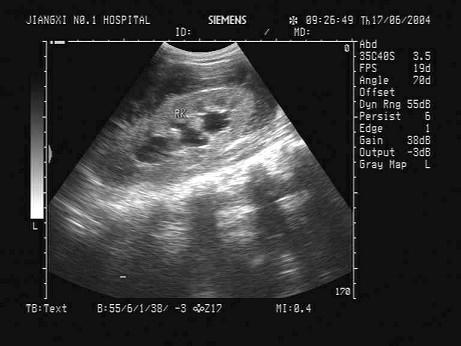

问题 某患者右肾区疼痛数日,体温38℃。根据该患者右肾声像图表现,最可能的超声诊断为?(?)

选项 A.肾周围炎 B.肾炎 C.肾结石 D.肾结核 E.肾周血肿

答案 A